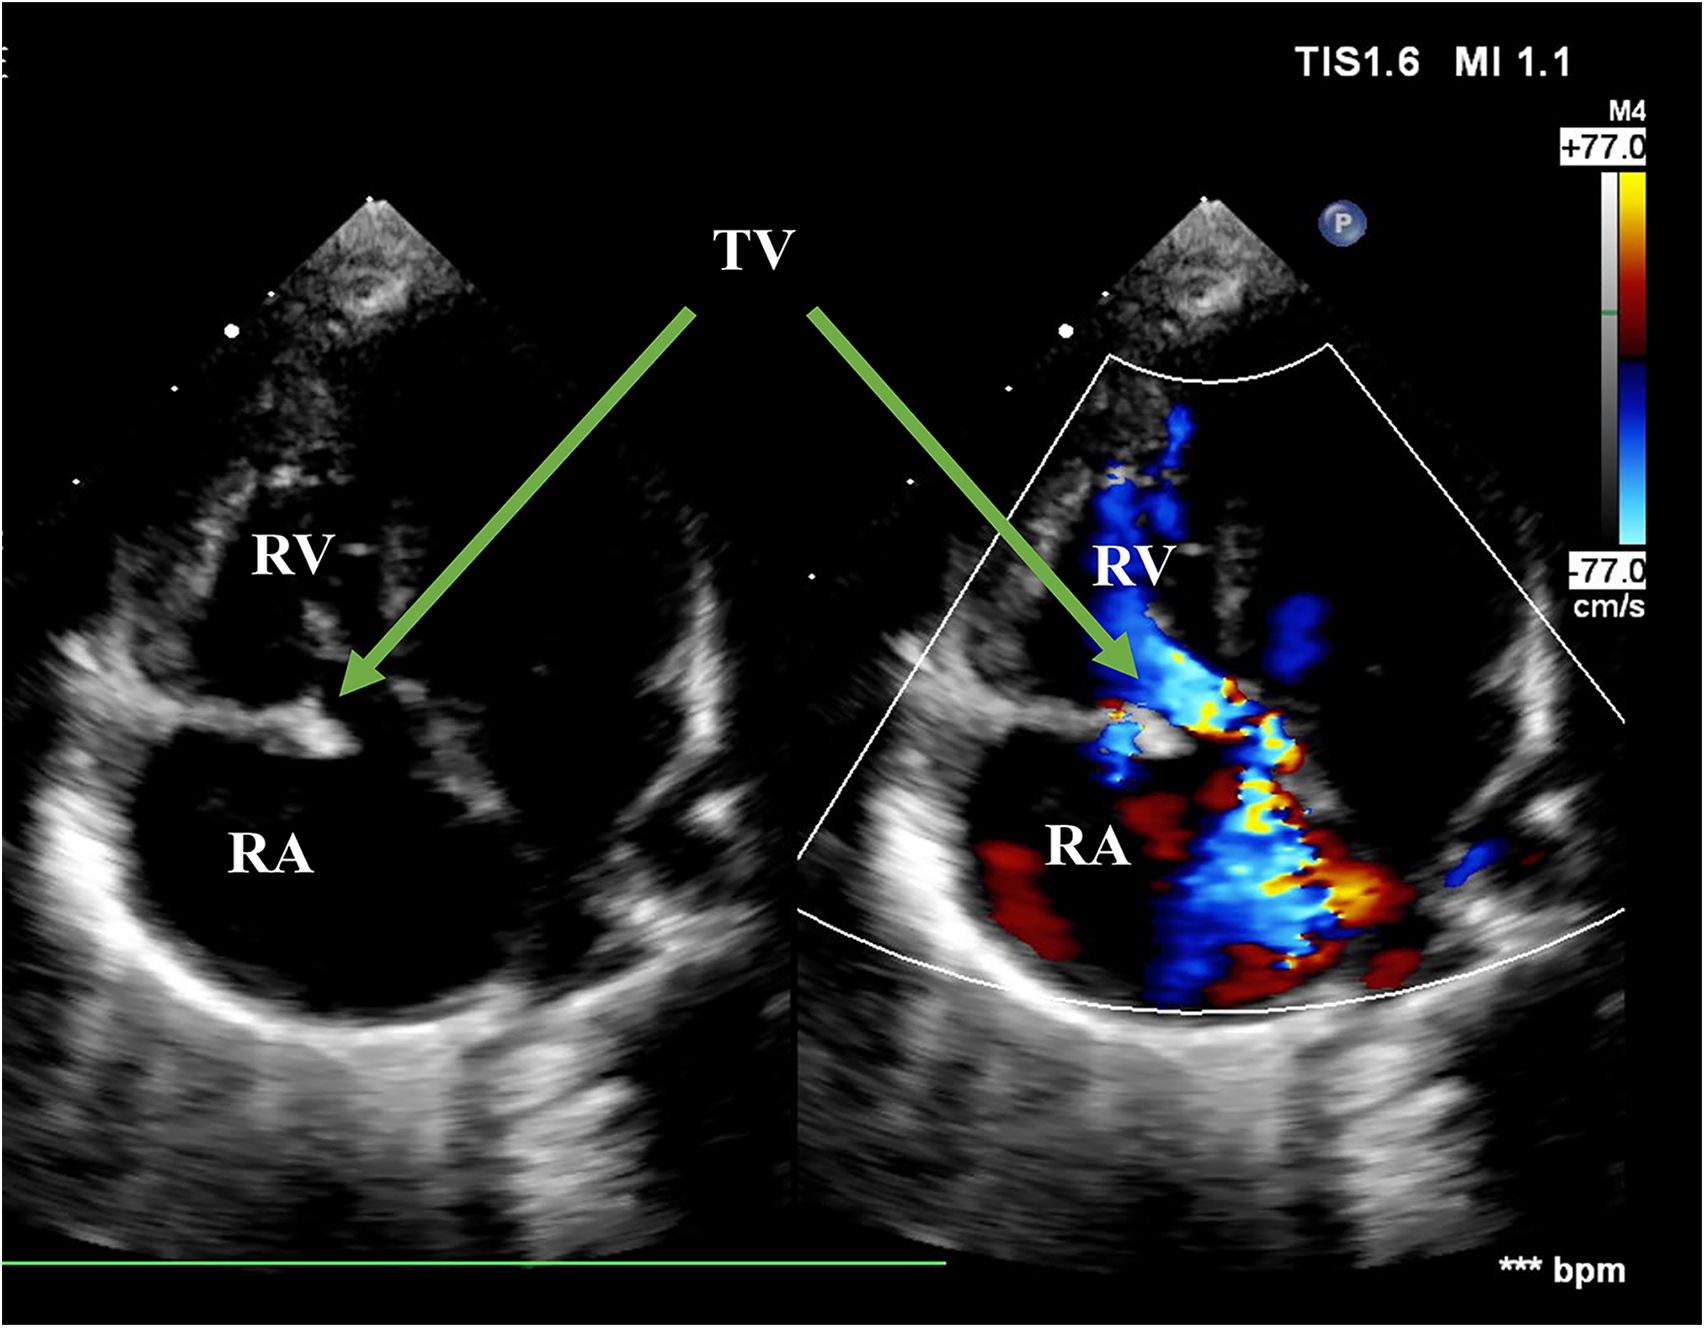

Figure 2

Echo before surgery in the A4C view. The picture showed flailed anterior leaflet prolapsing into the right atrium with a hyperechogenic mass. The green arrows pointed at flailed anterior leaflet of the tricuspid valve. RA, right atrium; RV, right ventricle; TV, tricuspid valve; A4C, apical four-chamber.

A 3,750-g full-term baby born by normal vaginal delivery was found with cyanosis with oxygen saturation of 46.6% and grade III/VI holosystolic murmurs in auscultation on the second day of life. Echocardiogram revealed prolapse of the anterior leaflet, restricted movement of the septal leaflet, and severe tricuspid regurgitation with a peak gradient pressure of 37 mmHg. The antegrade pulmonary flow was compromised with a right-to-left shunt patent foramen ovale (PFO). The diagnosis of the ruptured chordae tendineae was made by the flailed anterior leaflet of the TV with a thickened echogenic tip (Figures 1, 2). Electrocardiogram (ECG) results indicated enlargement of the right atrium and right ventricle. Contrast-enhanced MRI showed mild enlargement of the right atrium and right ventricle, mild pericardial effusion, and a tricuspid regurgitation fraction of 70%. The mother stated a history of normal pregnancy and denied using any drugs during pregnancy including prostaglandin synthetase inhibitors. She denied a family history of congenital heart disease or other hereditary diseases. The baby was stabilized by oxygen supplementation and the administration of milrinone.

Isolated tricuspid regurgitation caused by rupture of the papillary muscles or chordae tendineae is rare but fatal in newborns (5, 6). It is important to diagnose promptly through detailed examinations. Patients always present profound cyanosis as severe TR increases the pressure of the right atrium, leading to a large right-to-left shunt, similar to the hemodynamic performance of patients with pulmonary atresia. Echo is the preferred method to confirm a diagnosis. A typical Echo result reveals severe eccentric TR, PFO with right-to-left shunt, and compromised antegrade pulmonary flow at the parasternal short-axis view (PSAX). At the apical four-chamber (A4C) view, there are important findings that differentiate from Ebstein anomaly, including flailed anterior leaflet prolapse to the right atrium during the systolic phase and hyperechogenic papillary muscle lashing with the movement of the leaflet.